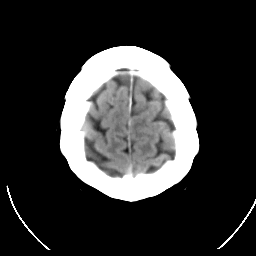

CT Study #1 -- Slice #21